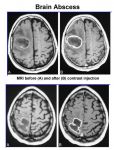

brain_abscess_text_jan_2007.jpgBrain Abcess

Brain abscess (or cerebral abscess) is an abscess caused by inflammation and collection of infected material, coming from local (ear infection, dental abscess, infection of paranasal sinuses, infection of the mastoid air cells of the temporal bone, epidural abscess) or remote (lung, heart, kidney etc.) infectious sources, within the brain tissue. The infection may also be introduced through a skull fracture following a head trauma or surgical procedures. Brain abscess is usually associated with congenital heart disease in young children. It may occur at any age but is most frequent in the third decade of life.